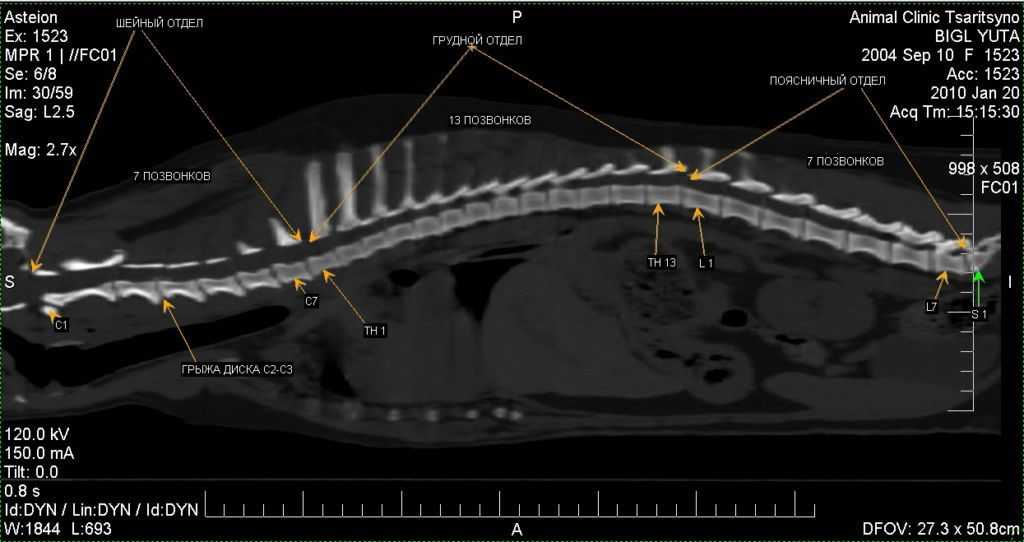

Межпозвоночная грыжа у собак – обнаруживается у животных в возрасте. При этом пол собаки не имеет особого значения. Межпозвоночная грыжа диагностируется у собак не часто. Характеризуется патологический процесс проникновением позвоночных хрящей в спинномозговой канал. Межпозвоночная грыжа провоцирует сильнейшие болезненные ощущения в спине, особенно во время движения собаки. Грыжа может поражать шейный отдел, грудной или крестцовый.

Если у питомца появились первые признаки дископатии, следует обратиться к ветеринару. Врач осматривает животное и назначает обследования. Для исключения проблем с позвоночником (переломы, опухоли и т.д.) делают рентген. Также при возможности делают компьютерную томографию или МРТ. Эти исследования позволяют наиболее точно увидеть состояние спинного мозга.

Дископатия на рентгене

Компьютерная томография применяется для диагностики травмы позвоночника и спинного мозга:

- информативна для оценки костных структур;

- на КТ возможна оценка паравертебральных тканей;

- в сочетании с контрастной миелографией КТ используется для оценки проходимости ликворных путей;

- применяется для оценки состояния позвоночного канала;

- ориентировочно — спинного мозга.

Но стоит понимать, что на КТ видны только костные структуры и практически не видны мягкотканые структуры и спинной мозг. Основное отличие КТ и МРТ состоит в разных физических явлениях, которые используются в аппаратах. В случае КТ — это рентгеновское излучение, которое дает представление о физическом состоянии вещества; МРТ — постоянное и пульсирующее магнитные поля, а также радиочастотное излучение, дающее информацию о распределении протонов (атомов водорода), т.е. о химическом строении тканей.